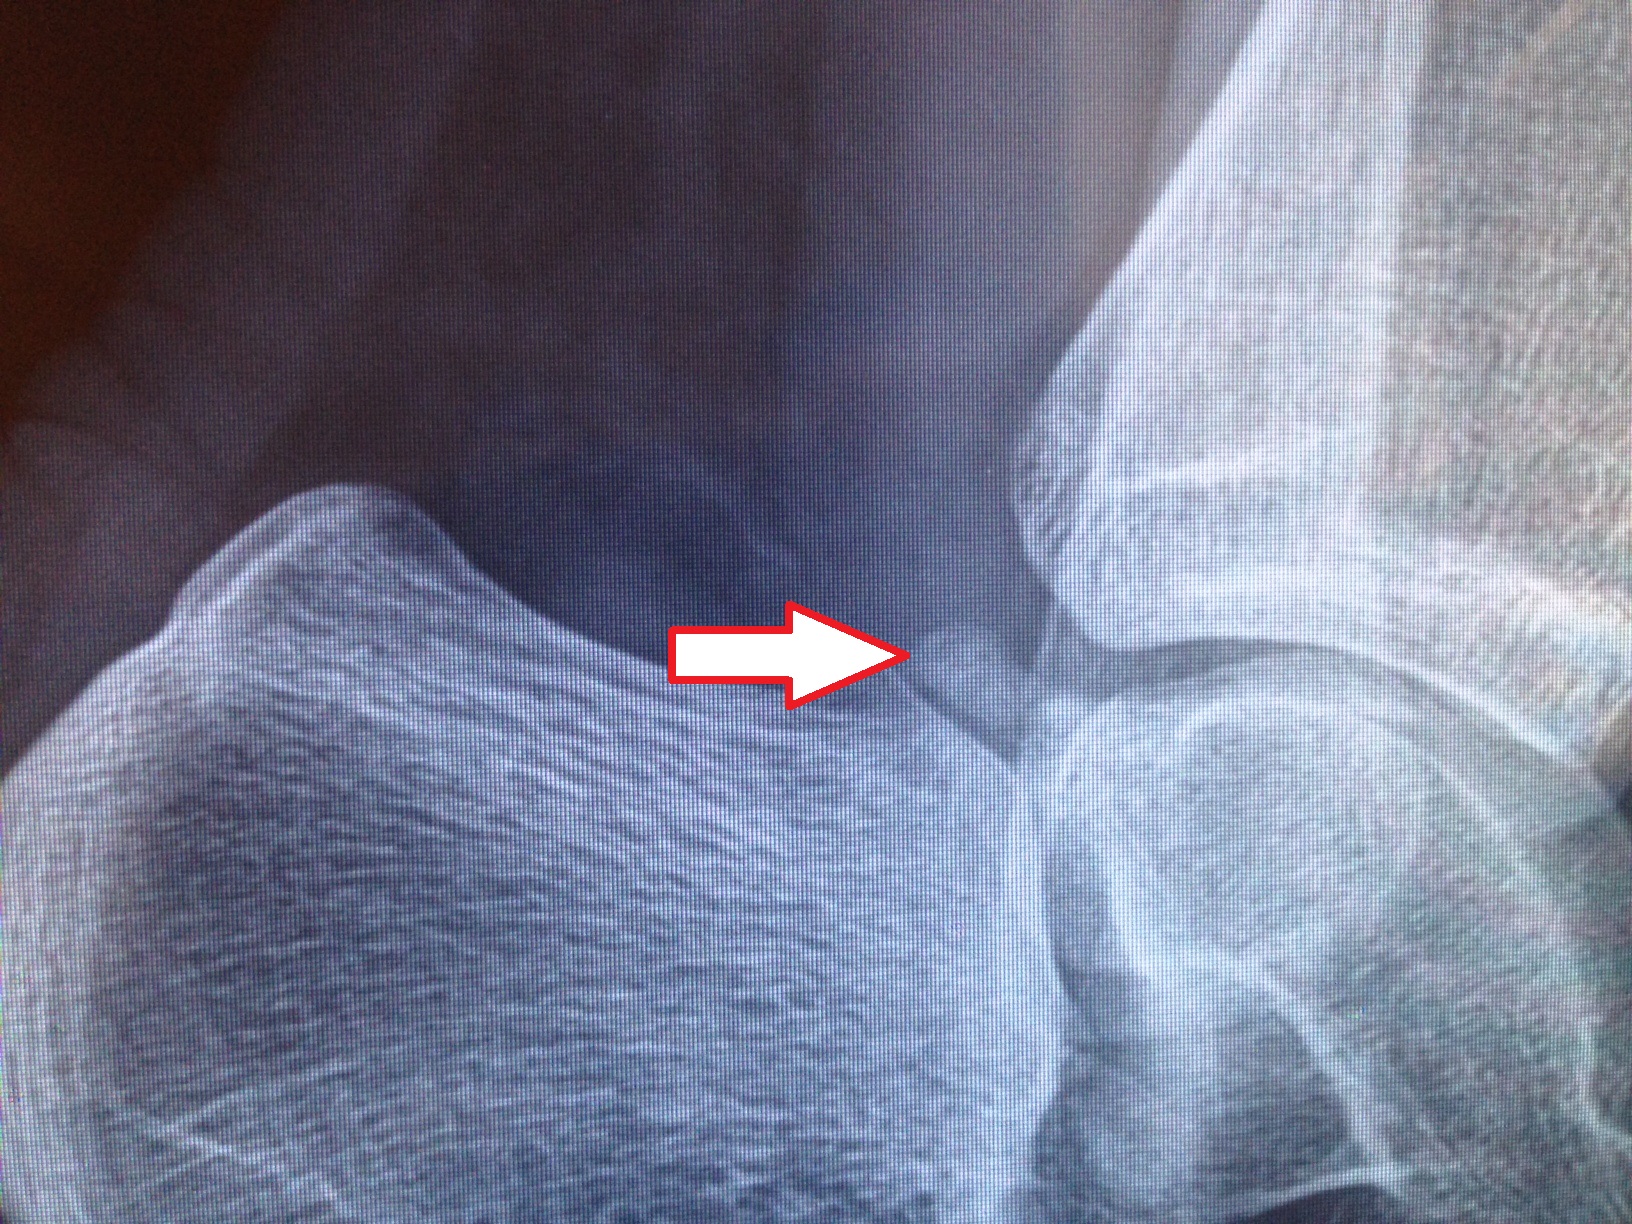

What Does An Os Trigonum Look Like?

An Os Trigonum can come in all kinds of shapes and sizes. Sometimes it is a tiny flat piece of bone, and sometimes it is quite large and round. Occasionally it is still attached to the main bone in the ankle (the Talus) but may also be completely detached. Some people have an "enlarged posterior process", that is not actually a separate bone, but does affect the range of motion in the ankle. The effect on your pointe range depends on the size and shape of the Os Trigonum.

How Do I Know If I Have An Os Trigonum?

The only way to really check if you have an Os Trigonum is to have an X-Ray or an MRI. This will have to be ordered by your doctor, and is usually only needed if you have ongoing pain in the back of the ankle. I often get dancers to get an X-Ray when standing on flat, one with their foot pointed, and one in pointe shoes (if appropriate) so that we can see how much the presence of the bone is interfering with their range of motion.